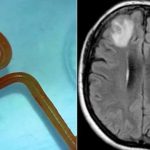

Egy jellemzően szőnyegmintás pitonokban élősködő fonálférget távolítottak el egy ausztrál nő agyából egy műtét során tavaly januárban; ez volt az első ilyen eset a világon – közölték ausztrál kutatók egy kedden nyilvánosságra hozott ...